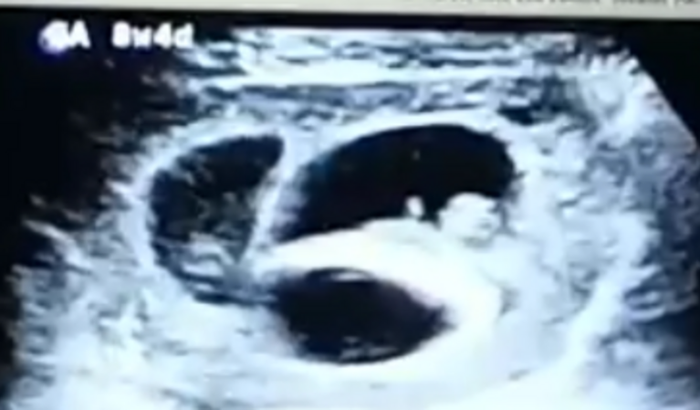

Olá! Me chamo Rosana, moro no Espírito Santo, criei essa vaquinha, para tentar arrecadar um valor para comprar o medicamento enoxoparina de 40mg, medicamento muito caro. Tenho 40 anos, estou grávida de trigêmeos, gravidez de alto risco, e tenho indicação do uso do medicamento até os bebês nascerem, tenho o anticoagulante lupico positivo, e tive um aborto da minha primeira gravidez, isso em 2001, mandei todos os documentos para tentar conseguir a medicação pelo SUS, onde o mesmo foi negado, querem que eu prove o aborto, isso tem 21 anos, o hospital que fiz a curetagem sofreu com a enchente de 2020,e perdeu tudo, mesmo provando com o exame e gravidez de alto risco, não consegui. No momento, por complicações da gravidez( sangramentos) o médico me afastou do trabalho, estou desde agosto sem receber, minha perícia só em novembro, onde, talvez eu consiga receber em dezembro, e, até lá, não temos como comprar esse medicamento só com o salário do meu esposo, espero do fundo do meu coração, que Deus toque o coração de cada um, para eu receber essa ajuda e condeguir comprar meu medicamento. Desde já, agradeço! Confio em Deus que irei conseguir!🙏Lutei muito para conseguir engravidar, e depois de 2 anos, Deus nos abençoou com 3❤, sei que Ele proverá!!🙏🙏